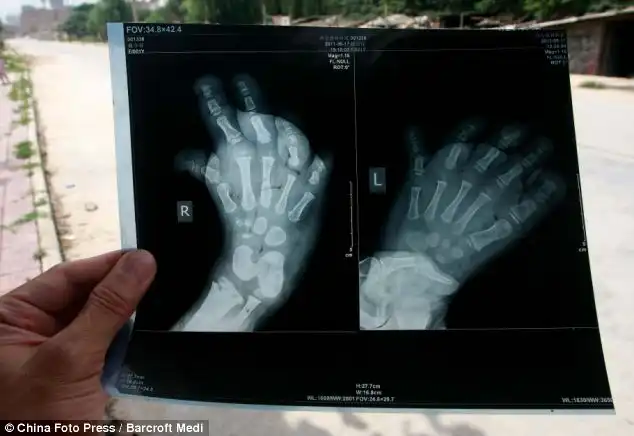

Эта 3-х летняя китаянка не может носить обувь из-за природной аномалии…

Врачи не знают что происходит с ногами девочки,ноги постоянно растут.